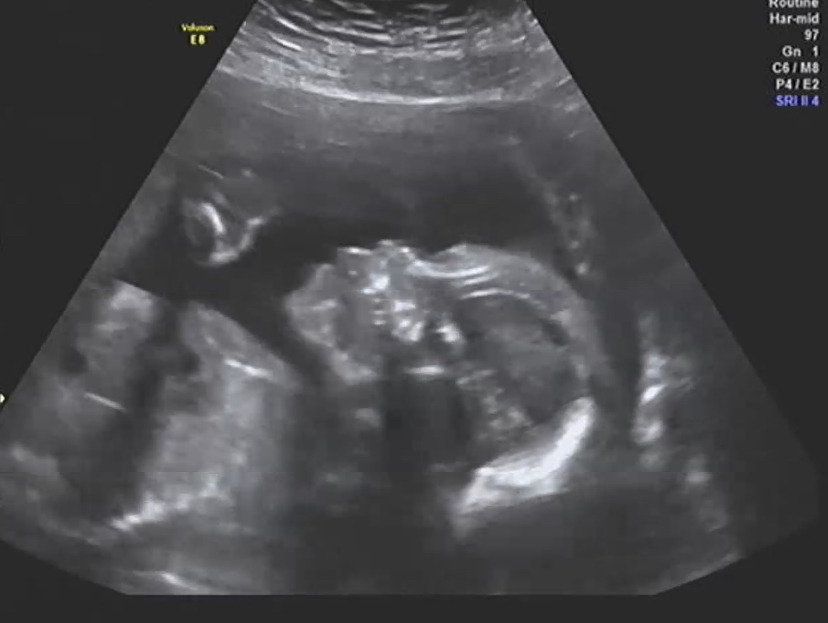

우리 아기 21주 정밀 검사 결과... 아들로 밝혀져!

아기 콧대를 보기 위해 각도를 돌리다가 본 옆모습!

임신 초기에는 2주에 한 번씩 산부인과에 가고 초음파를 봤다면 임신 중기에 들어서면 4주에 한 번씩 병원에 간다. 12주 - 16주 - 21주 - 24주 - 28주 이런 식으로 가면서 갈 때마다 이런저런 검사들을 하는데 이번 주에는 21주 차 정밀 검사가 있었다.

21주 차 정밀 검사에서는 머릿속부터 발끝까지 아주 찬찬히 아기를 둘러보면서 이상이 없는지 확인한다. 뇌는 양쪽 다 잘 형성되었는지, 안구에는 문제없는지, 심장은 좌심방 좌심실 우심방 우심실 다 잘 있는지, 장기 하나하나, 손가락 발가락 다 본다.

다행히 우리 아기는 모든 게 다 정상! 기분 좋게 이상 없다는 소견을 들었다. 주치의 선생님 왈.. "범이 엄마, 축하해요! 아기는 모두 건강하네요! 그런데.. 다리 사이.. 보셨죠?;..." 라며 위로를 해주셨다. 하하하...!

딸과 함께 원피스 맞춰 입으며 꽁냥꽁냥 한 미래를 그렸던 나인데.. 다리 사이에 선명한 무언가를 보고야 말았다.. 호호^^ 나도 이래 저래 아쉬웠지만 내 머리로 딸내미 머리 묶어주는 연습을 하던 남편도 & 마트에서 귀여운 딸내미들 드레스를 보며 설레었다는 시어머니도 쪼끔 아쉬워하셨다.. 허허..!